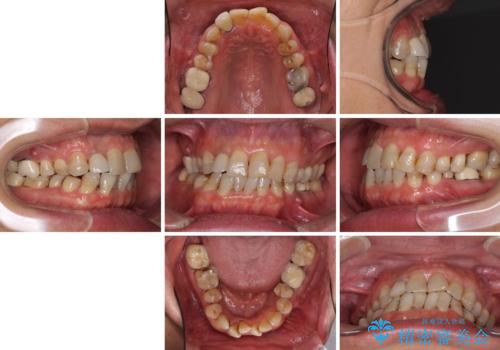

- 前歯のデコボコや、奥歯を咬んだときに痛みがあるとのことで来院された患者様です。

全体的に問題が多く、全てをしっかりと治療したいとのことでした。

全体的に中等度の歯周病と診断されたため、歯周外科処置やインプラントによる咬合回復から進めて行き、矯正治療による歯列改善を行った後にオールセラミッククラウンにて補綴することとしました。